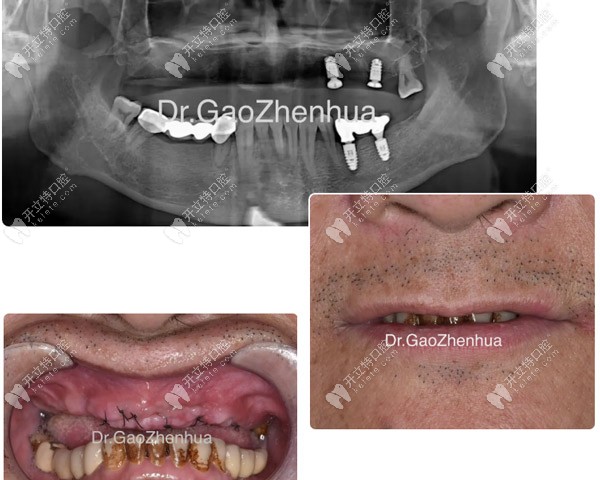

馮先生決定來(lái)鼎植治療缺骨問(wèn)題,是因?yàn)?span style="color: rgb(255, 0, 0);">一年前做的6顆即刻負(fù)重短植體全部松動(dòng)脫落,在廣州各大口腔尋醫(yī)無(wú)效后才去的治療。

馮先生種植失敗后拍的CT片

馮先生種植失敗后拍的CT片▲

結(jié)果顯示:牙槽嵴多處缺骨、牙齒骨質(zhì)疏松,后牙區(qū)多位點(diǎn)缺骨并與竇腔貫連,好在結(jié)節(jié)翼板區(qū)骨量尚可。

顴種植位點(diǎn)不得已還是放在貫通位點(diǎn),竇底適當(dāng)植骨,前牙區(qū)靠鼻底硬骨板雙皮質(zhì)固位獲得穩(wěn)定性,經(jīng)過(guò)2個(gè)小時(shí)的手術(shù),實(shí)現(xiàn)了即刻負(fù)重的預(yù)期!

當(dāng)天做完VIIV穿顴穿翼手術(shù)

當(dāng)天做完VIIV穿顴穿翼手術(shù)▲